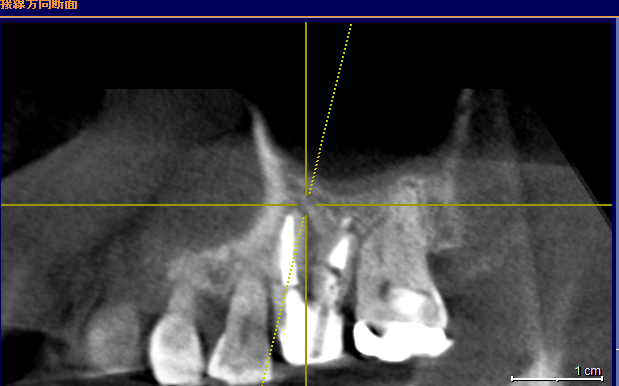

から ↓先週の画像

この状態。

嬉しい!!MTAで根管充填

骨が出来ています。上顎洞も治っています。